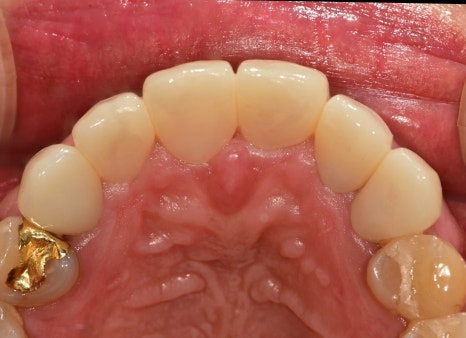

위에서 바라보았을 때도 전과 다르게

아주 이상적인 아치형을 그리고 있습니다,

정면에서 보았을 때도 정중선이 잘 맞고

치아가 대칭적으

로 형태도 맞으며 환자분께서

너무 밝지 않은 자연스러운 색상을 원하셔서

그 범위 내에서 밝은색으로 완성이 되었습니다.